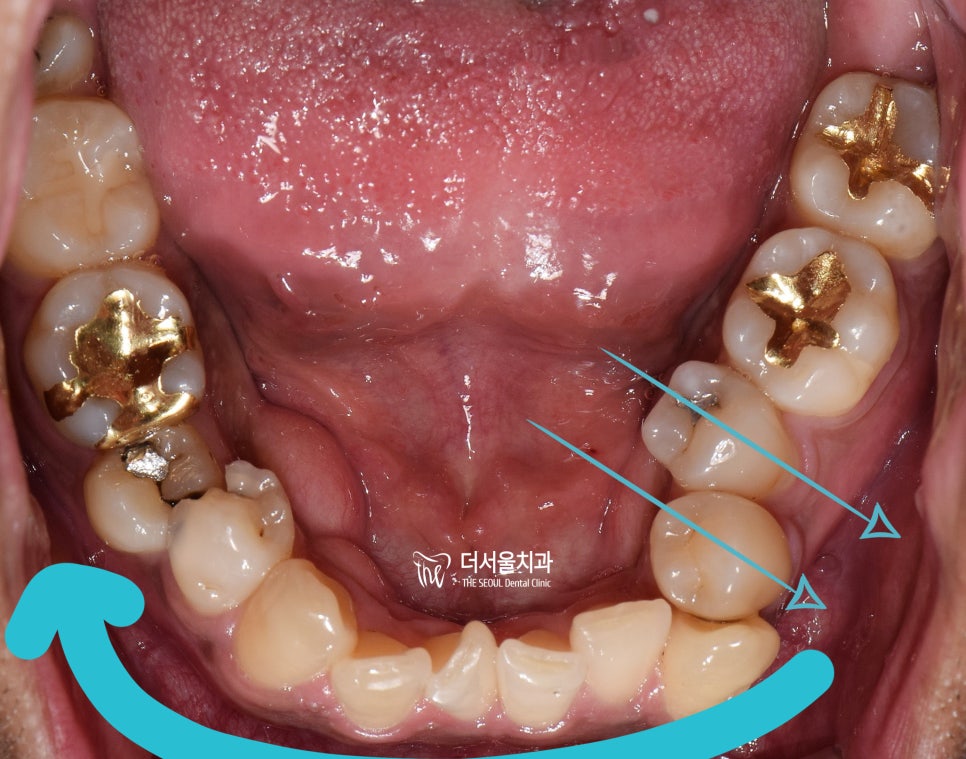

그러면서 하악에서도,

치열의 불규칙성이 같이 관찰되는데

결국 이런 치열들 때문에,

발치를 결정할 수 밖에 없었고

양측으로 동시에 발치를 하는게 아닌,

#14, 44번 치아만 발치하는

편측발치로 진행을 하게 될 상황입니다.

『한번 더 정리』

편측 발치를 해야 되는 이유는,

아래 사진 2장에서 보실 수 있습니다.